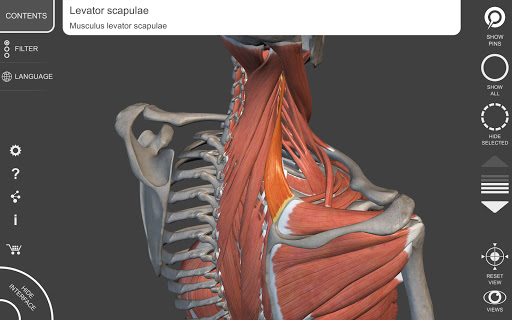

"Anatomy 3D Atlas" cho phép bạn nghiên cứu giải phẫu người theo cách dễ dàng và tương tác.

Thông qua giao diện đơn giản và trực quan, bạn có thể quan sát mọi cấu trúc giải phẫu từ mọi góc độ.

Các mô hình giải phẫu 3D đặc biệt chi tiết và có kết cấu lên đến độ phân giải 4k.

• Hệ thống cơ xương

• Xoay và phóng to từng mô hình trong không gian 3D

• Hình dung các cơ qua các lớp từ lớp nông đến lớp sâu nhất

• Bằng cách chọn một mô hình hoặc một ghim, thuật ngữ giải phẫu liên quan sẽ hiển thị

• Mô tả các cơ: nguồn gốc, chèn, chi phối thần kinh và hành động